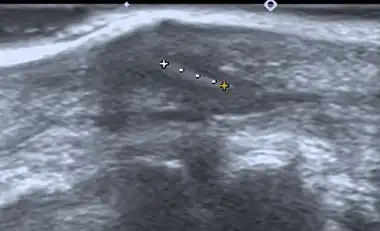

- Medical ultrasonography – used to locate glass, metal, pencil graphite, some plastics, stone, and some types of wood.[6]

Small wooden splinters (1–4 mm) distant from bones are most easily detected by ultrasonography, while CT scan and magnetic resonance imaging have higher sensitivity for those near bones.[7]